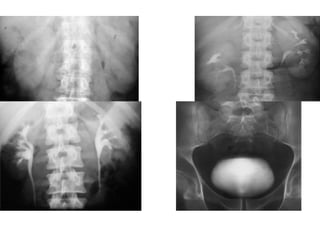

X-QUANG HỆ NIỆU

KUB

• Mục đích:

Đánh giá vôi hóa bất thường của hệ

niệu

Đánh giá tình trạng ổ bụng

Bất thường hệ thống xương

—Kỹ thuật:

Chuẩn bị bệnh nhân:

Tư thế BN : nằm ngửa, phim chụp AP

Yêu cầu: lấy từ cực trên thận đến hết

khớp mu.

• Phân tích kết quả:

- Thận

- Bất thường đậm độ

đường niệu

- Dải mỡ cơ thắt lưng

chậu

- Tình trạng ổ bụng

- Hệ thống xương

• Hạn chế:

- Độ nhạy và độ đặc hiệu phát

hiện sỏi hệ niệu không cao ( ≤

60%) do : sỏi nhỏ, sỏi không cản

quang, trùng lắp vào xương…

- Cần phân biệt với nhiều

nguyên nhân vôi hóa khác trong

ổ bụng ( Vôi hóa TM chậu:

Phlebolith,…)